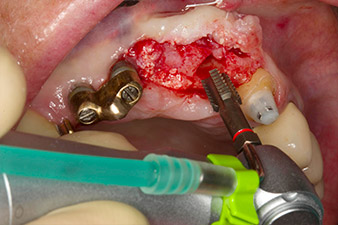

Avvitamento con il manipolo contrangolo WS-75L

Fig. 3: Avvitamento con il manipolo contrangolo WS-75L a una velocità di 20:1 (programma P4). La coppia elevata di Implantmed, con sistema di bloccaggio esagonale per trasmissione di potenza affidabile e inversione automatica della direzione di rotazione al raggiungimento di una resistenza troppo elevata, si è rivelata particolarmente utile in questo caso.

Posizionamento motorizzato dell'impianto

Fig. 4: Posizionamento motorizzato dell'impianto con il manipolo contrangolo WS-75L a una velocità di 20:1 (programma P5).